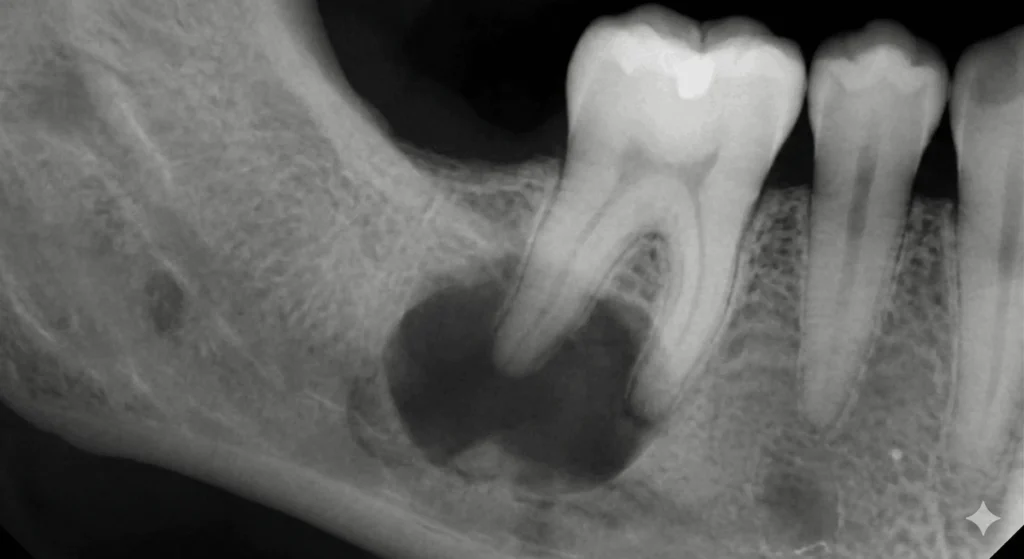

Sometimes, patients feel no pain, but routine dental X-rays reveal bone loss or infection around the root tip. This is why regular dental checkups are important.

Understanding when retreatment is necessary can help prevent severe complications such as bone loss, abscess formation, or tooth extraction.

Ignoring signs of infection can lead to: